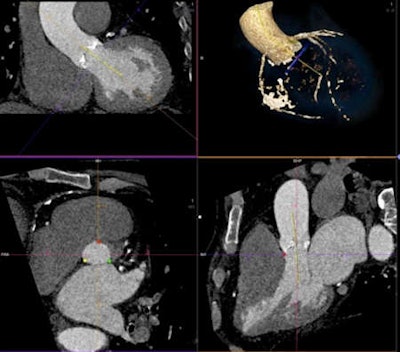

The study Becker discussed in his presentation, led by his colleague Dr. Bernard Bischoff and published in June, looked at 40 patients with severe symptomatic aortic valve stenosis who underwent CT for TAVI procedure planning. The first 20 consecutive patients (mean age 78 ± 7 years, mean body mass index [BMI] 25.6) were scanned on a second-generation dual-source CT (DSCT) system (Somatom Definition Flash, Siemens Healthcare) using a high-pitch scan mode (pitch value 3.4) and 60 mL of contrast agent.

The second group of 20 patients (mean age 80 ± 7 years, mean BMI 25.1) were examined using a 128-slice single-source CT system (Somatom Definition Edge, Siemens Healthcare), a high-pitch scan mode (pitch value of 1.7), and 60 ml of contrast agent (Imeron 350, Bracco Diagnostics) (International Journal of Cardiovascular Imaging, June 2013, Vol. 29:5, pp. 1159-1165).

The results showed a minor but significant difference in the overall image quality score with lower image quality in single-source CT (3.5 ± 0.6) compared with DSCT (3.85 ± 0.4; p = 0.037). Mean image quality was higher for DSCT (mean score 4.0) compared with single-source CT (mean score 3.5, p = 0.001) for comparing the coronary ostia.

"The image quality was less for the coronary ostia and the ascending aorta, mostly due to the fact we had no ECG triggering for single-source CT, but overall, what can be said was that the images were reliable enough to perform the procedure with single-source CT as well as with DSCT," Becker said.

There was no significant difference in evaluating the aortic valve and annulus, or the image quality of the iliofemoral arteries, and signal intensity and noise did not differ significantly between groups, Becker noted.